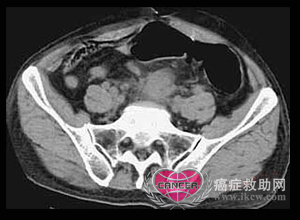

直肠癌患者除早期无症状外,大部分患者都有不同程度的临床表现。 直肠中段癌,广泛盆腔淋巴结转移

直肠中段癌,广泛盆腔淋巴结转移

①CT对局部浸润广泛的直肠癌及直肠癌术后盆腔复发的诊断有所帮助,可以直接观察是否肿瘤侵犯盆腔肌肉(提肛肌、闭孔内肌、梨状肌等)、膀胱、前列腺。肌肉轮廓消失或体积增大常提示肿瘤侵犯肌肉。盆骨受侵时则表现为浸润性骨质破坏。膀胱有腔外性肿块存在时,应考虑为膀胱受浸润。术后3个月时可作一盆腔CT检查,作为基础片,以便日后随访时对照用。如日后CT片示软组织增大,其凸面向前,软组织中央出现低密度区或弥散性钙化,则可能有复发。当诊断不确定时,可在CT引导下作细针吸取细胞学诊断。